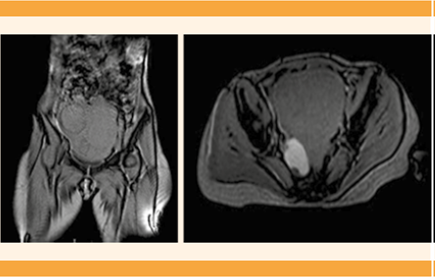

Paciente de 51 años, nulípara, sin antecedentes personales de interés para el padecimiento actual; con una cirugía mamaria por causas estéticas y hemitiroidectomía por hiperplasia nodular. Entre sus características antropométricas se reportaron: estatura de 1.60 m, peso de 55 kg e índice de masa corporal de 21.48 kg/m2. Acudió a revisión ginecológica por elevación de los marcadores tumorales CA-125 (93 U/mL) y CA-19.9 (114 U/mL) y dolor abdominal en la fosa ilíaca derecha de varios meses de evolución. Debido a la dificultad de la exploración ecográfica por vaginismo, se decidió solicitar la resonancia magnética abdominopélvica (pues la abdominal tampoco permitía la delimitación y correcta visualización de los órganos pélvicos), que reportó: útero aumentado de tamaño, comprimido y desplazado por dos masas miomatosas subserosas con escaso componente intramural, una de 60 mm en el lado derecho y la otra de localización un poco más superior de 70 mm (que en su interior tenía una pequeña zona sugerente de degeneración quística). Además, se visualizaban múltiples lesiones de características similares intramurales de menor tamaño. En el anexo derecho se apreciaba una lesión de características quísticas, compatible con endometrioma ovárico derecho de 48 x 30 x 40 mm, aproximadamente, y otra formación de similares características y comportamiento de señal de 12 mm anterolateral, respecto al primero. Se estableció el diagnóstico de útero polimiomatoso y sospecha de endometrioma en el ovario derecho (Figura 1). Se decidió la histerectomía total con salpingooforectomía bilateral por laparotomía, que trascurrió sin complicaciones. Entre los hallazgos intraoperatorios se observaron múltiples adherencias intestinales que bloqueaban el fondo de saco de Douglas, por lo que se decidió conservar el cuello del útero, debido al alto riesgo de lesión intestinal. El reporte definitivo del estudio anatomopatológico de las piezas quirúrgicas demostró la coexistencia de múltiples leiomiomas en el miometrio, algunos con focos de esclerosis, endometrio proliferativo y pólipo endometrial, además del diagnóstico de endometriosis en ambos ovarios y la coexistencia de un tumor de Brenner benigno en el ovario izquierdo. En la pieza de anexectomía bilateral se encontraron, en el estudio microscópico, sobre todo en la región distal fímbrica, focos de carcinoma intraepitelial tubárico seroso, sin identificarse signos histológicos de invasión estromal ni depósitos tumorales en la superficie ovárica ni en la serosa uterina. El análisis inmunohistoquímico reportó positividad en las células tumorales para WT1, apreciándose con Ki67 alto índice de proliferación (Figura 2). Debido a la asociación de este tipo de lesiones con la mutación en la línea germinal BRCA 1 y 2, se solicitó el estudio genético. En la actualidad, los controles mamográficos, la citología cervical y el marcador tumoral CA-125 se encuentran dentro de los parámetros de referencia, la paciente permanece en seguimiento en la Unidad de Ginecología Oncológica, a la espera del reporte de genética.

Figura 1 Resonancia magnética en fase T1 que muestra el útero polimiomatoso con lesión en la porción derecha, de 70 x 63 x 63 mm. En la zona anexial derecha se objetiva una lesión compatible con endometrioma ovárico, de 48 x 30 x 40 mm.